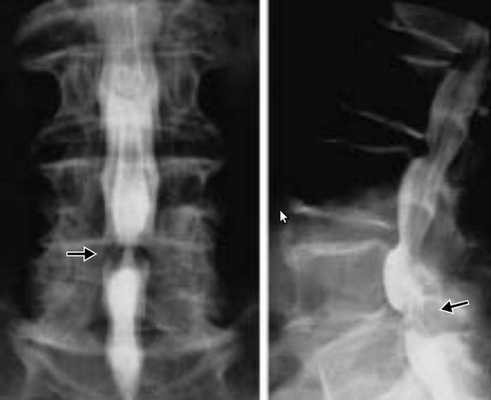

В шейном отделе позвоночника данную особенность костной структуры канала можно обнаружить на боковых рентгенограммах путем расчета и оценки индекса М.Н.Чайковского. Индекс Чайковского — это отношение сагиттального размера позвоночного канала к сагиттальному размеру тела позвонка на уровне данного конкретного позвонка без учета краевых костных разрастаний. На рентгенограмме измеряется сагиттальный диаметр позвоночного канала (а) и сагиттальный размер тела позвонка (б), первое число делится на второе (а:б).

Измерение сагиттального размера позвоночного канала и тела позвонка